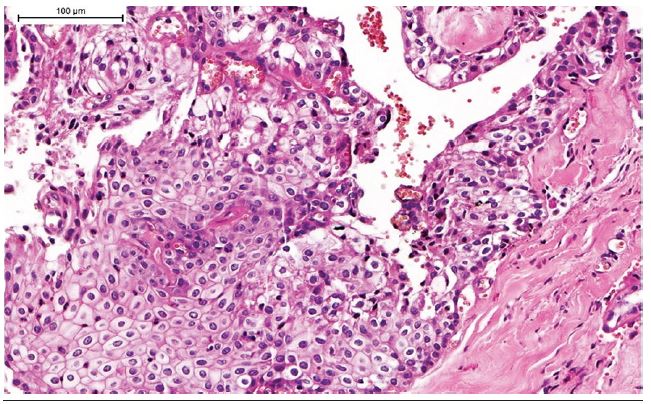

An incisional biopsy was performed and histopathological examination revealed a neoplasm mainly formed by solid islands of cells with epidermoid, intermediate and clear morphology, which exhibited different degrees of pleomorphism (Figure 3).